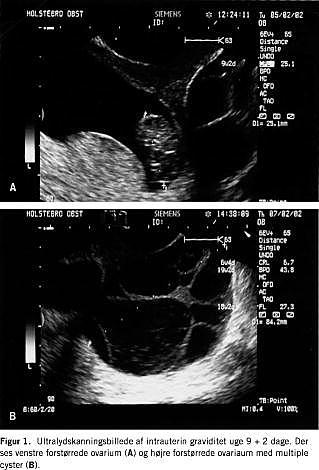

En 31-årig kvinde havde tidligere fået foretaget konisering på grund af svær dysplasi. Hun var gravid i første cyklus efter p-pille-seponering og sås første gang ambulant med førstetrimester blødning. En vaginal ultralydsskanning viste intrauterint beliggende gestationssæk med et fosteranlæg på 8,5 mm svarende til en gestationsalder på seks uger og seks dage. Begge ovarier blev fundet normale. Ved en ambulant kontrol to uger senere havde patienten kraftige subjektive graviditetssymptomer i form af kvalme og brystspænding. Paraklinisk fandtes kraftig forhøjet s-humant choriongonadotropin (hCG): 348.344 IE/l, steget fra 130.225 IE/l en uge tidligere. En vaginal ultralydskanning viste intrauterin gestationssæk med et fosteranlæg på 17 mm. Ved næste ambulante kontrol svarende til en gestationsalder på ni uger og to dage viste en vaginal ultralydsskanning et tydeligt fosteranlæg på 25 mm med hjerteaktion. Derudover sås ovarierne at være forstørrede til henholdsvis 7 cm og 10 cm i diameter med multiple store cyster, der fuldstændig lignede ovarielt hyperstimulation. Der var ingen fri væske i fossa Douglassi og ingen acsites (Figur 1 ). Patienten var alment upåvirket.